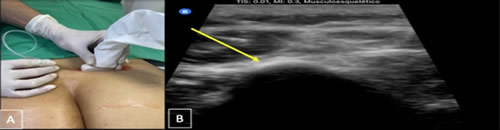

Se realizó un estudio de tipo observacional, retrospectivo, en pacientes diagnosticados con dolor lumbar crónico, signos y síntomas de atrapamiento de nervios cluneales o clunealgía llevados a bloqueo. Se revisaron las historias clínicas obteniendo información demográfica y clínica. Los criterios de inclusión son pacientes mayores de 18 años de edad con antecedente de patología lumbar por imágenes de resonancia o radiografía, con uno o más síntomas, dolor lumbar, irradiación a glúteo o miembro inferior, disestesia, exacerbación del dolor con cambios en la postura lumbar, y/o signos de clunealgía evidenciados en el examen físico de la historia clínica, a quienes se les realizó bloqueo analgésico de nervios cluneales (Figura 1 A y B) en el Hospital Universitario San José y Clínica Los Nogales en Bogotá durante el 1 de septiembre de 2019 al 31 de abril de 2021. Se excluyeron pacientes a quienes se les realizó otro tipo de procedimiento analgésico tipo bloqueos de bandas miofasciales y bloqueos facetarios con mejoría del dolor.

Fig. 1. A. Técnica de abordaje guiado por ultrasonido en los dos hospitales. Paciente en decúbito prono, transductor de alta frecuencia sobre el plano transversal de espina ilíaca posterior, la fascia toracolumbar y el borde lateral del músculo erector de la columna, al final del glúteo mayor se observa el glúteo medio conocido este punto como túnel graso. B: se realiza infiltración de medial a lateral al nivel de la espina ilíaca posterosuperior y sobre fascia toracolumbar, en el nervio cluneal superior (flecha amarilla) con solución analgésica con lidocaína al 1 % sin epinefrina 100 mg o bupivacaína al 0,25 % + betametasona 6 mg (volumen total 5 mililitros) a nivel perineural e interfascial. Observando la fascia toracolumbar y el músculo erector de espina separarse.